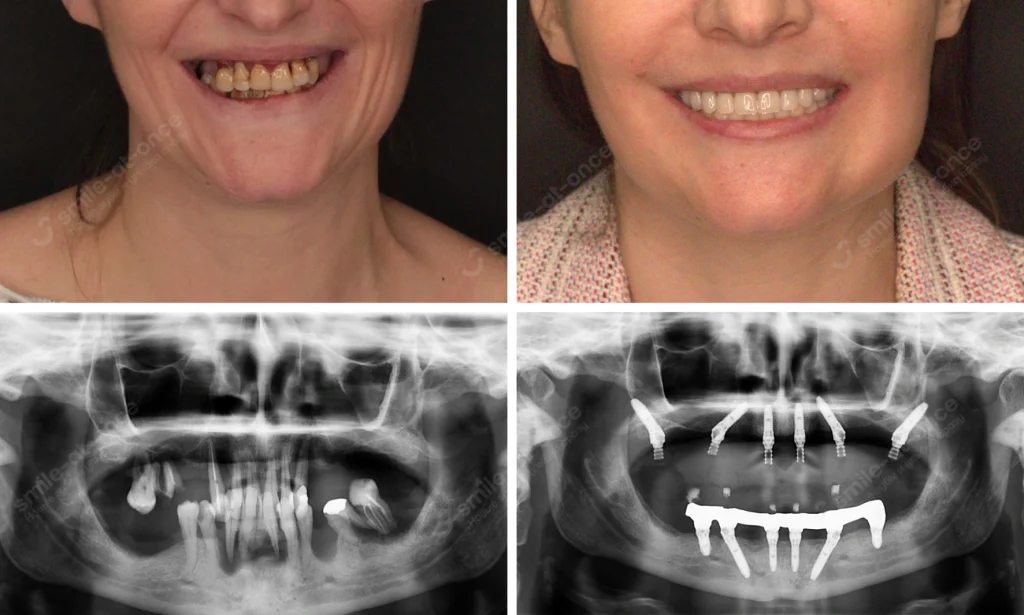

Ко мне обратился Сергей, 59 лет. Верхняя челюсть — выраженная атрофия, костная пластика в прошлом не прижилась. Мы выбрали скуловые импланты (Zygoma) и немедленную нагрузку. На 3-й день Сергей ушёл с адаптационным несъёмным протезом. Реакция? «Я снова ем суп нормальной ложкой, а не чайной — и не прячу улыбку». Реабилитация после имплантации заняла 2 недели до полного бытового комфорта, а к постоянной работе перешли через 11 месяцев.

Марина, 32 года, потеряла резец. Сразу сделали одномоментную имплантацию, использовали PRF-мембраны. На 8 неделе — красивая диоксид циркониевая коронка. Как сказала Марина: «Да, было страшно, но всё оказалось проще, чем у стоматолога в детстве».

Анатолий, 64 года. Подвижность II–III степени, больно жевать. За 1 день удалили безнадёжные зубы, поставили 6 имплантов и зафиксировали адаптационный протез. Через 2 недели он пришёл с фразой: «Я могу кусать котлету. И я снова смеюсь». Это и есть цель.